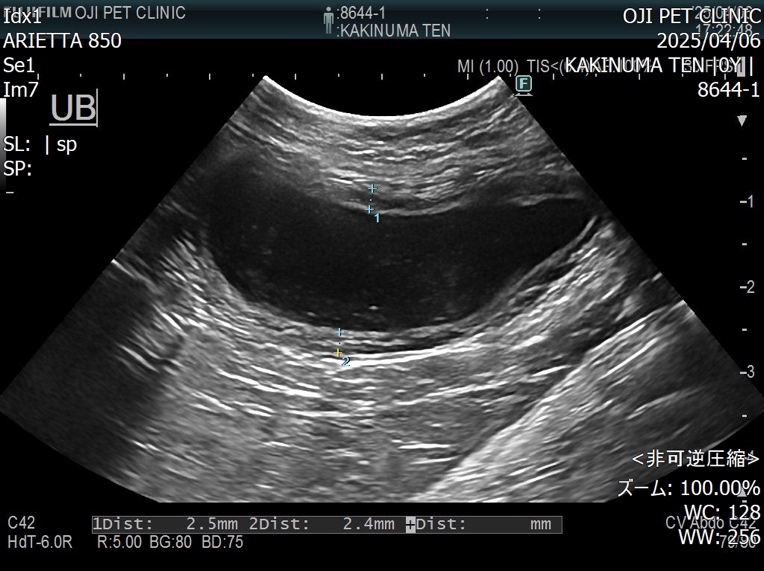

超音波検査にて膀胱内には結石が認められないことを確認